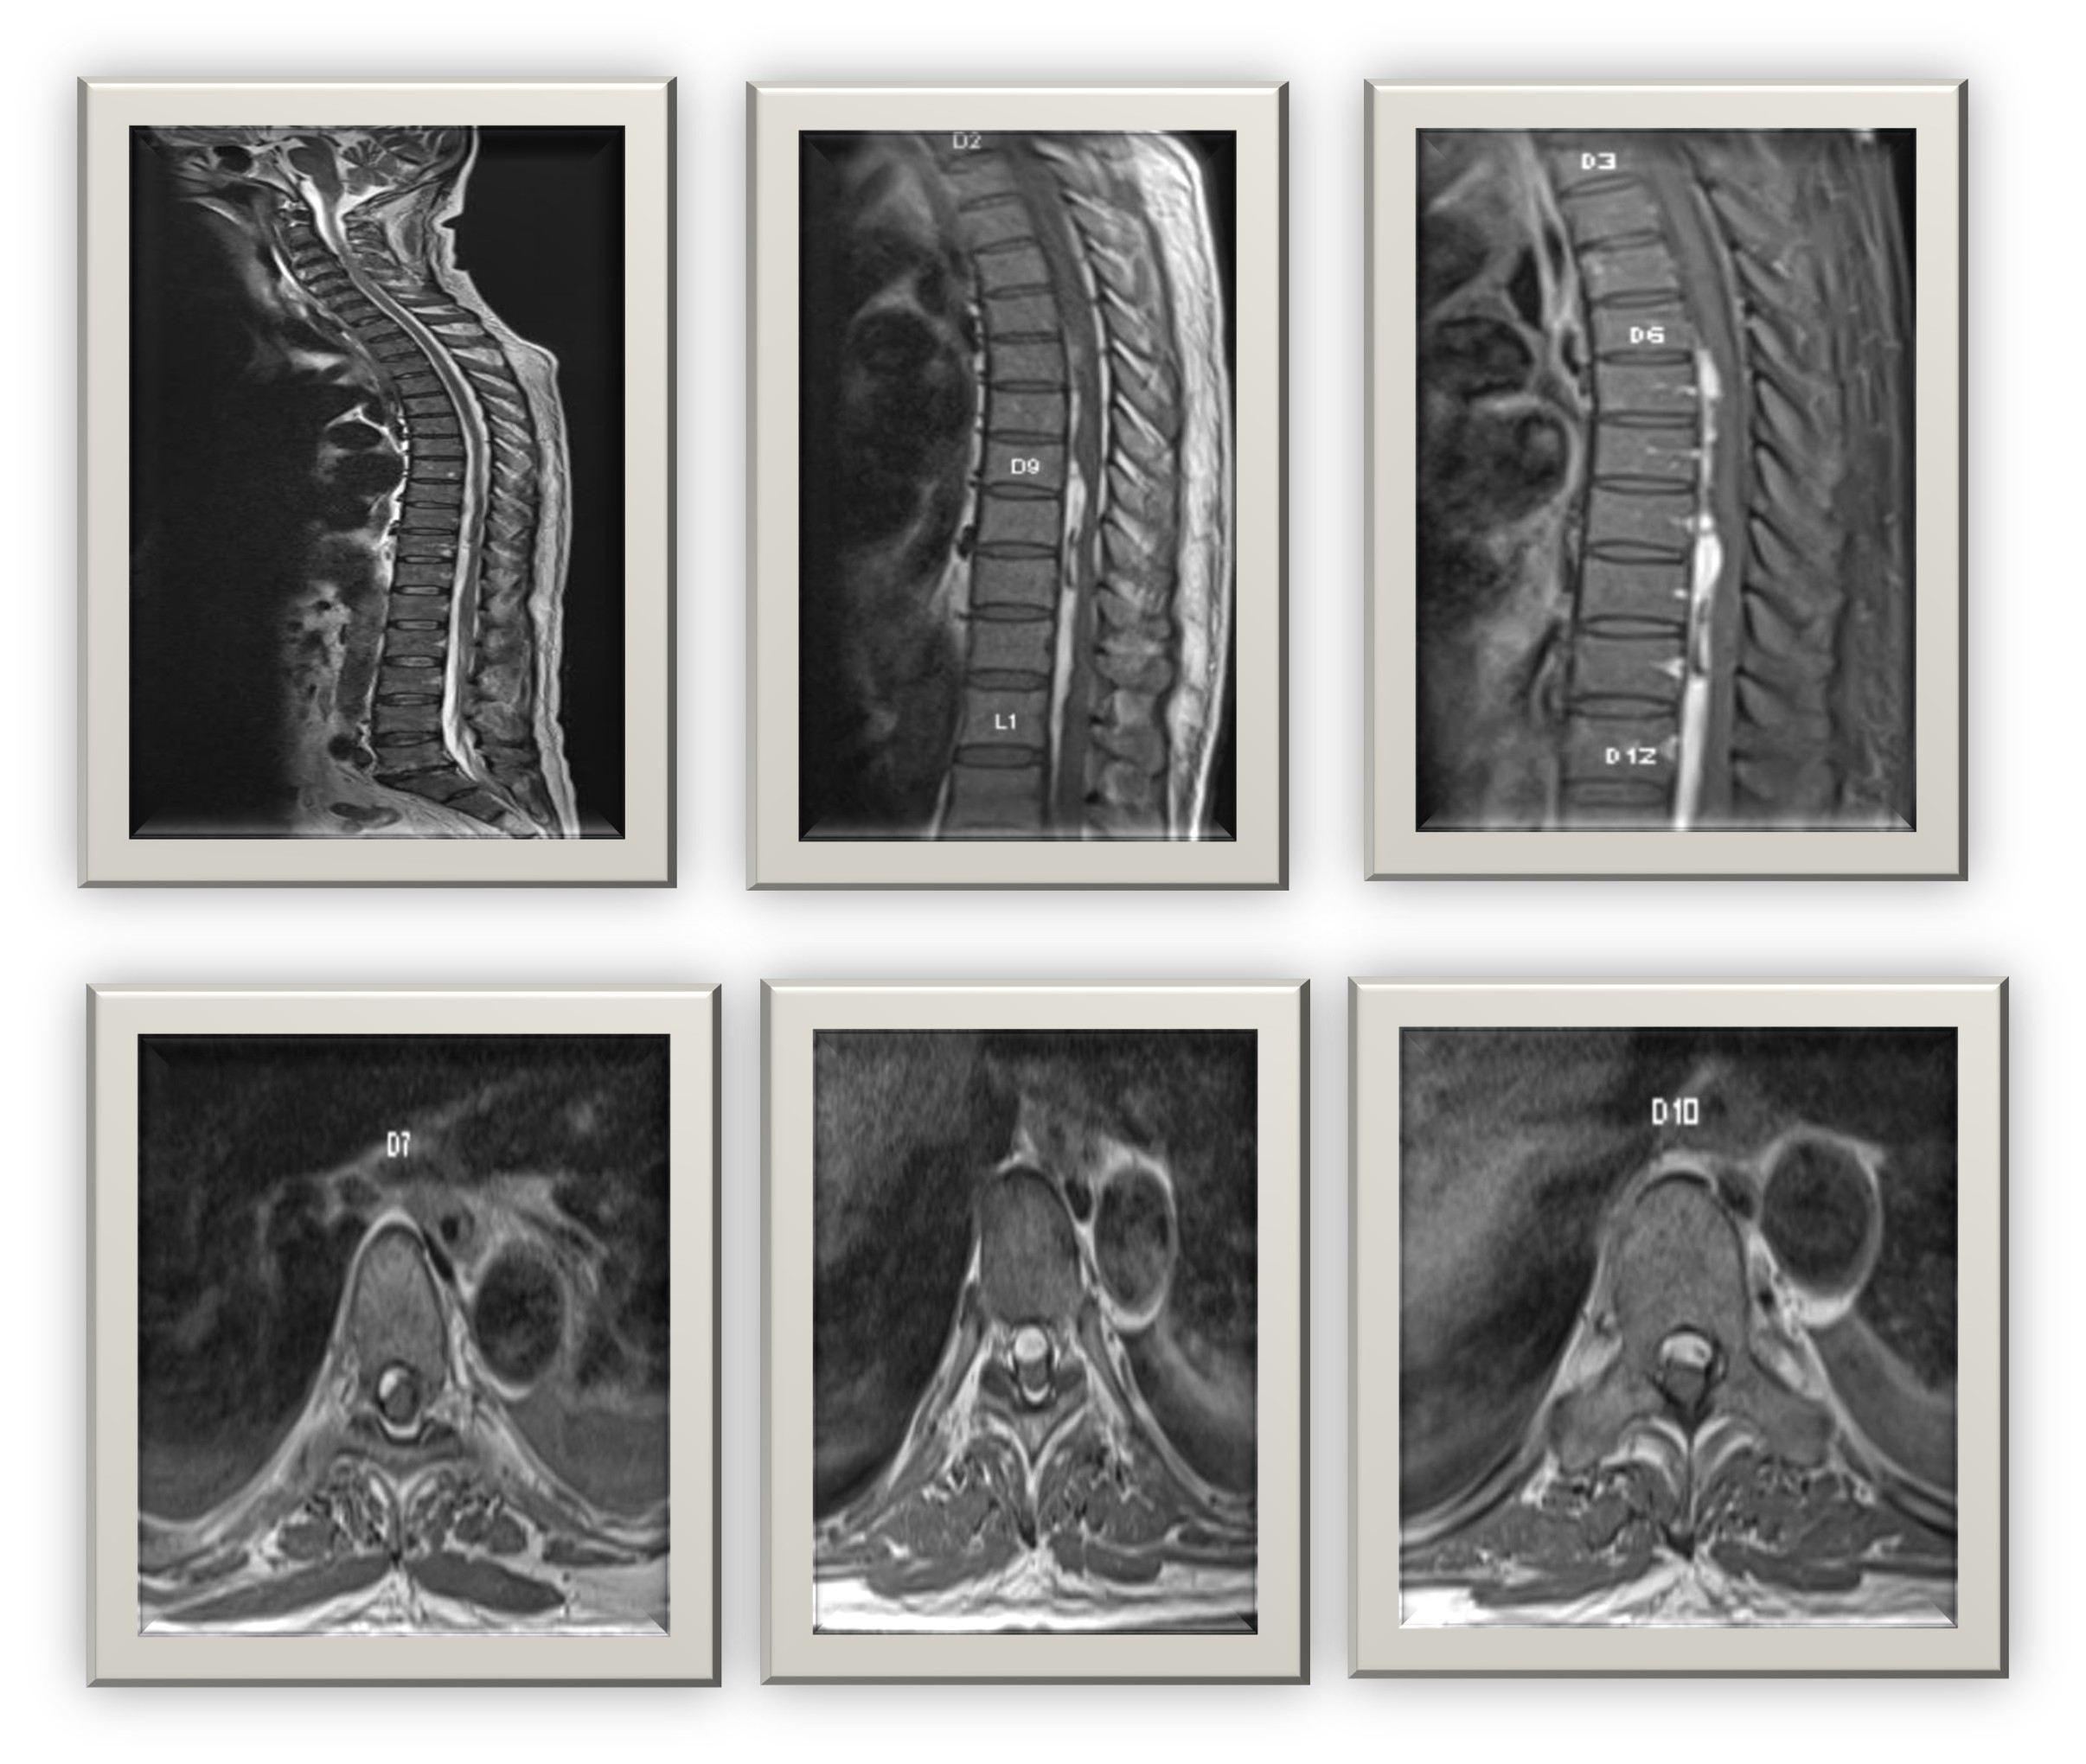

MRI Spine: Multiple cystic lesions in the thoracic and lumbar vertebrae with paravertebral and epidural extension, suggestive of infective spondylodiscitis.

MRI Brain: Ring-enhancing lesion in the right frontoparietal region with surrounding edema consistent with cerebral abscess or meningoencephalitis.

The negative cultures and serologies created diagnostic uncertainty. Imaging played a pivotal role in guiding diagnosis. MRI findings showing ring-enhancing lesions in both spine and brain raised suspicion of disseminated bacterial infection or neurotuberculosis. However, the acute presentation and neutrophilic response favoured a pyogenic etiology.

Neurological manifestations emerged later, emphasizing how systemic infections can evolve to involve the CNS. The ring-enhancing lesion seen on MRI, along with clinical response to antibiotics, confirmed an infective meningoencephalitis component.

Imaging correlation (especially MRI) is invaluable when systemic infections involve the CNS or spine.